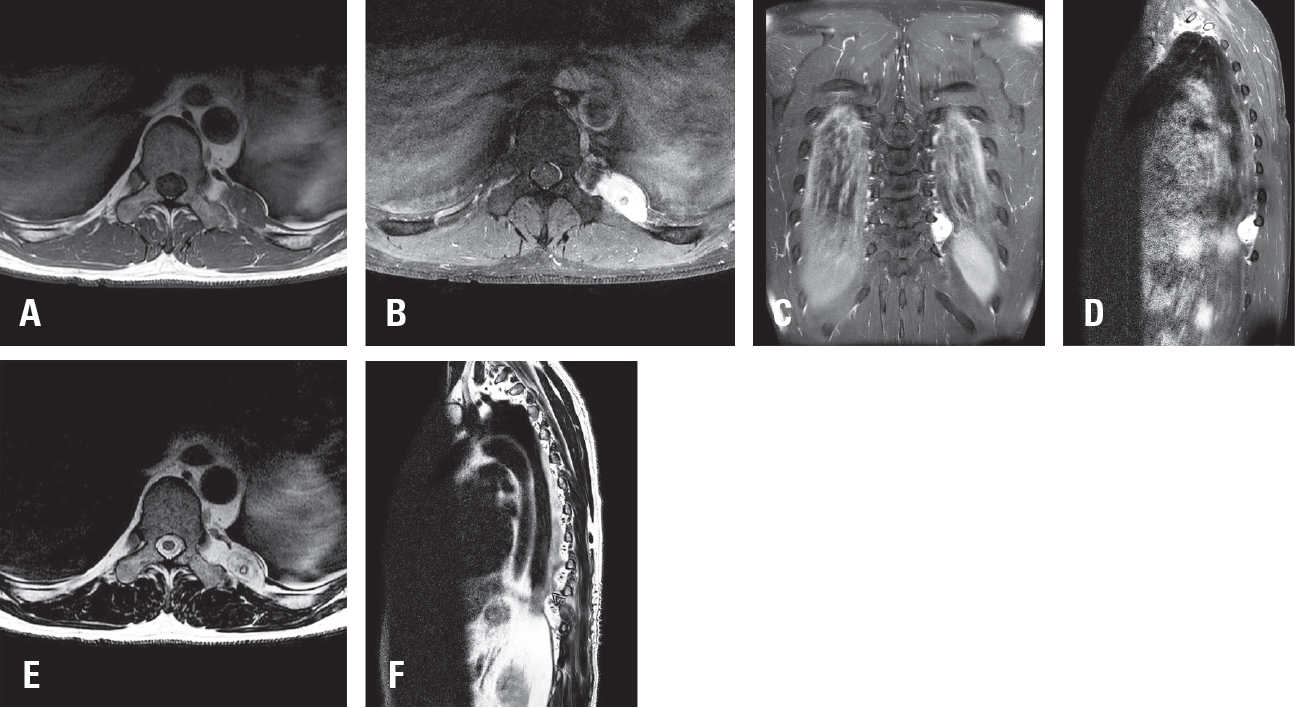

Spinal artery aneurysms are exceedingly rare, and their natural history remains poorly understood. Diagnosis can be challenging due to their small size and the difficulty in detection by MR angiography (MRA) or CT angiography (CTA); Digital Subtraction Angiography (DSA) is considered the gold standard diagnostic tool. This case report presents two cases of ruptured thoracic radicular artery aneurysms leading to subdural hematoma (SDH) and subarachnoid hemorrhage (SAH). The first patient, a 71-year-old female, presented with bilateral leg weakness, headache, and severe back pain, where multiple fusiform dilatations of the left T9 radiculopial artery were identified. She showed significant improvement after surgical intervention. The second patient, a 75-year-old female, presented with paraplegia and severe back pain, and a saccular dilatation in the right T10 radiculopial artery was found. She underwent endovascular embolization but showed no neurological improvement. These cases highlight the diverse clinical presentations, diagnostic challenges, and uncertainties in management strategies for ruptured spinal artery aneurysms, emphasizing the need for prompt intervention, especially in cases with significant or progressive neurological deficits.